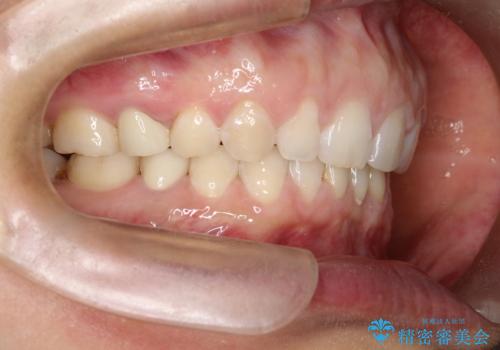

【空隙歯列】ワイヤー矯正で短期間に治療を終えたい

- 歯と歯の間に隙間があることを主訴に来院されました。

短期間での治療終了を希望され、ワイヤー矯正にて治療を行い1年ほどで治療を終了しております。

下顎前歯は矯正後補綴治療を行なっております。